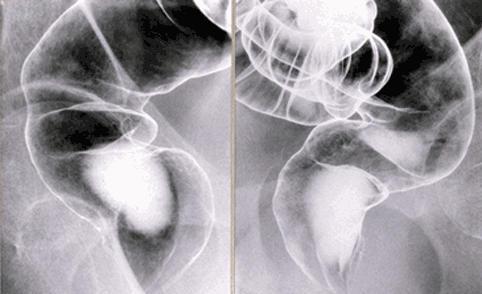

Rectal mucosal prolapse syndrome with multiple flat-elevated lesions.

Inflammatory or ulcerative disease / lesions/Rectal mucosal prolapse syndrome

Large intestine(Colon)/Rectum

X-ray

20 - 24